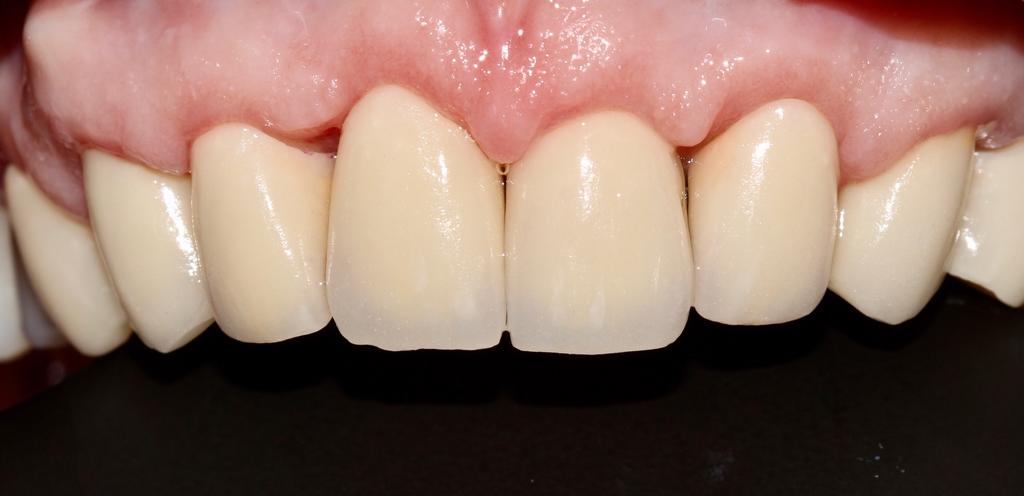

Коронки из оксида циркония

В программе EXOCAD смоделирована работа на верхней челюсти. Фронтальные зубы редуцированы. И нанесена керамическая масса вручную.